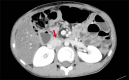

The role of surgical management for chronic pancreatitis in providing pain relief and improving quality of life is significant. Surgical techniques involving pancreatic head resection scored more over the drainage procedures. Among the resection procedures, Frey's procedure received widespread acceptance. However, the exact extent of pancreatic head resection to be performed and the limits of the resection are still debatable. The present report of bile duct preserving pancreatic head resection (BDPPHR) describes an innovative approach to the pancreatic head and conclusively defines the extent of head resection. The simplicity, feasibility and easy reproducibility of the BDPPHR is also reiterated.